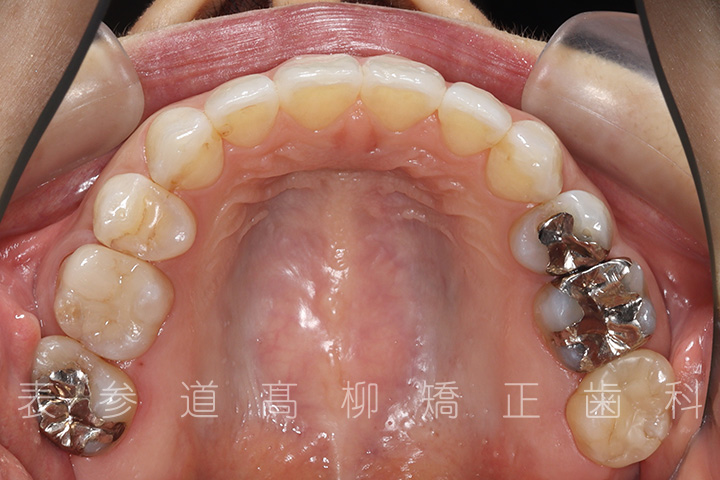

口呼吸と舌癖で前歯が咬み合わない患者様の症例をご紹介いたします。

・前歯部開咬

・上顎前突(前歯の前方傾斜)

・上下前歯部叢生(凸凹歯並び)

・口呼吸、舌癖

術前術後の比較